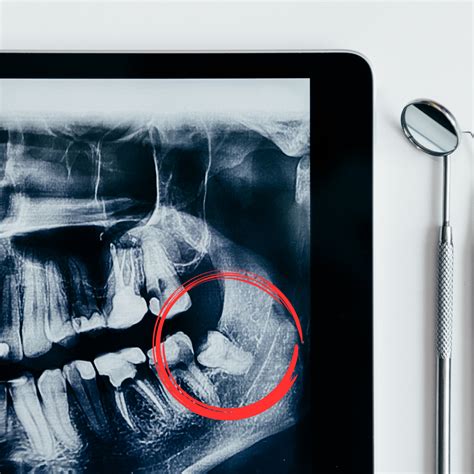

Aunque la exodoncia es una práctica muy habitual en cualquier clínica dental, hay veces en las que este simple procedimiento puede convertirse en un proceso más complicado. El odontólogo deberá identificar cuándo es necesario realizar una exodoncia compleja. En estos casos, el especialista tendrá decidir qué dientes deben extraerse y cuáles no, así como el tipo de cirugía oral que va a emplear. Sin duda, los casos más frecuentes por los que se realiza una exodoncia compleja son las extracciones de las muelas del juicio o los dientes incluidos. Muchas veces, estas piezas suelen alojarse en el interior de los maxilares. En otras ocasiones, la posición es incorrecta o no tienen suficiente espacio para salir, lo que provoca la malposición de otros dientes. Otros casos muy habituales de extracciones dentales complejas tienen que ver con la malformación de raíces y los dientes rotados o en muy mal estado.

El Proceso de Extracción de las Muelas del Juicio

La extracción de las muelas del juicio es una intervención quirúrgica frecuente en la edad adulta. Aunque suele tratarse de una cirugía ambulatoria sencilla, el proceso de recuperación varía según cada persona y puede generar dudas: ¿cuánto dura la inflamación? ¿Cuántos días de reposo se necesitan? ¿Qué complicaciones pueden aparecer?

Estos dientes suelen aparecer entre los 17 y los 25 años de edad, aunque algunas personas nunca desarrollan las muelas del juicio. Muchas personas sufren la impactación de las muelas del juicio. Esto se produce cuando las muelas del juicio no tienen suficiente espacio para erupcionar en la boca o para desarrollarse normalmente.

Antes de extraer las muelas del juicio el dentista hará una valoración al paciente y decidirá si es necesario hacerlo o no. Los terceros molares o muelas del juicio son los últimos dientes en salir. La erupción ocurre entre los 17 y 25 años. Sin embargo, para este momento es posible que tengan problemas para salir.

A esa edad los demás dientes ya se han posicionado en su sitio y es posible que no quede espacio para los terceros molares. En consecuencia, estos no pueden salir y desarrollarse con normalidad. Cuando esto ocurre se les llama muelas de juicio impactadas.

Los molares impactados pueden crecer en forma horizontal o en distintos ángulos respecto a la mandíbula. En ocasiones permanecen retenidos, lo que puede provocar daños en las raíces de las piezas adyacentes. También puede ocurrir que salgan solo de forma parcial, lo que favorece la acumulación de alimentos y bacterias.

Hay algunas señales que advierten sobre la necesidad de extraer las muelas del juicio. Por ejemplo, si aparecen quistes o tumores, dolor, caries, periodontitis o si han dañado los dientes vecinos. No siempre es necesario extraer las muelas del juicio. Si estas han salido por completo y en una posición adecuada no es preciso hacerlo. Hay que considerar también que permitan mantener una higiene correcta.